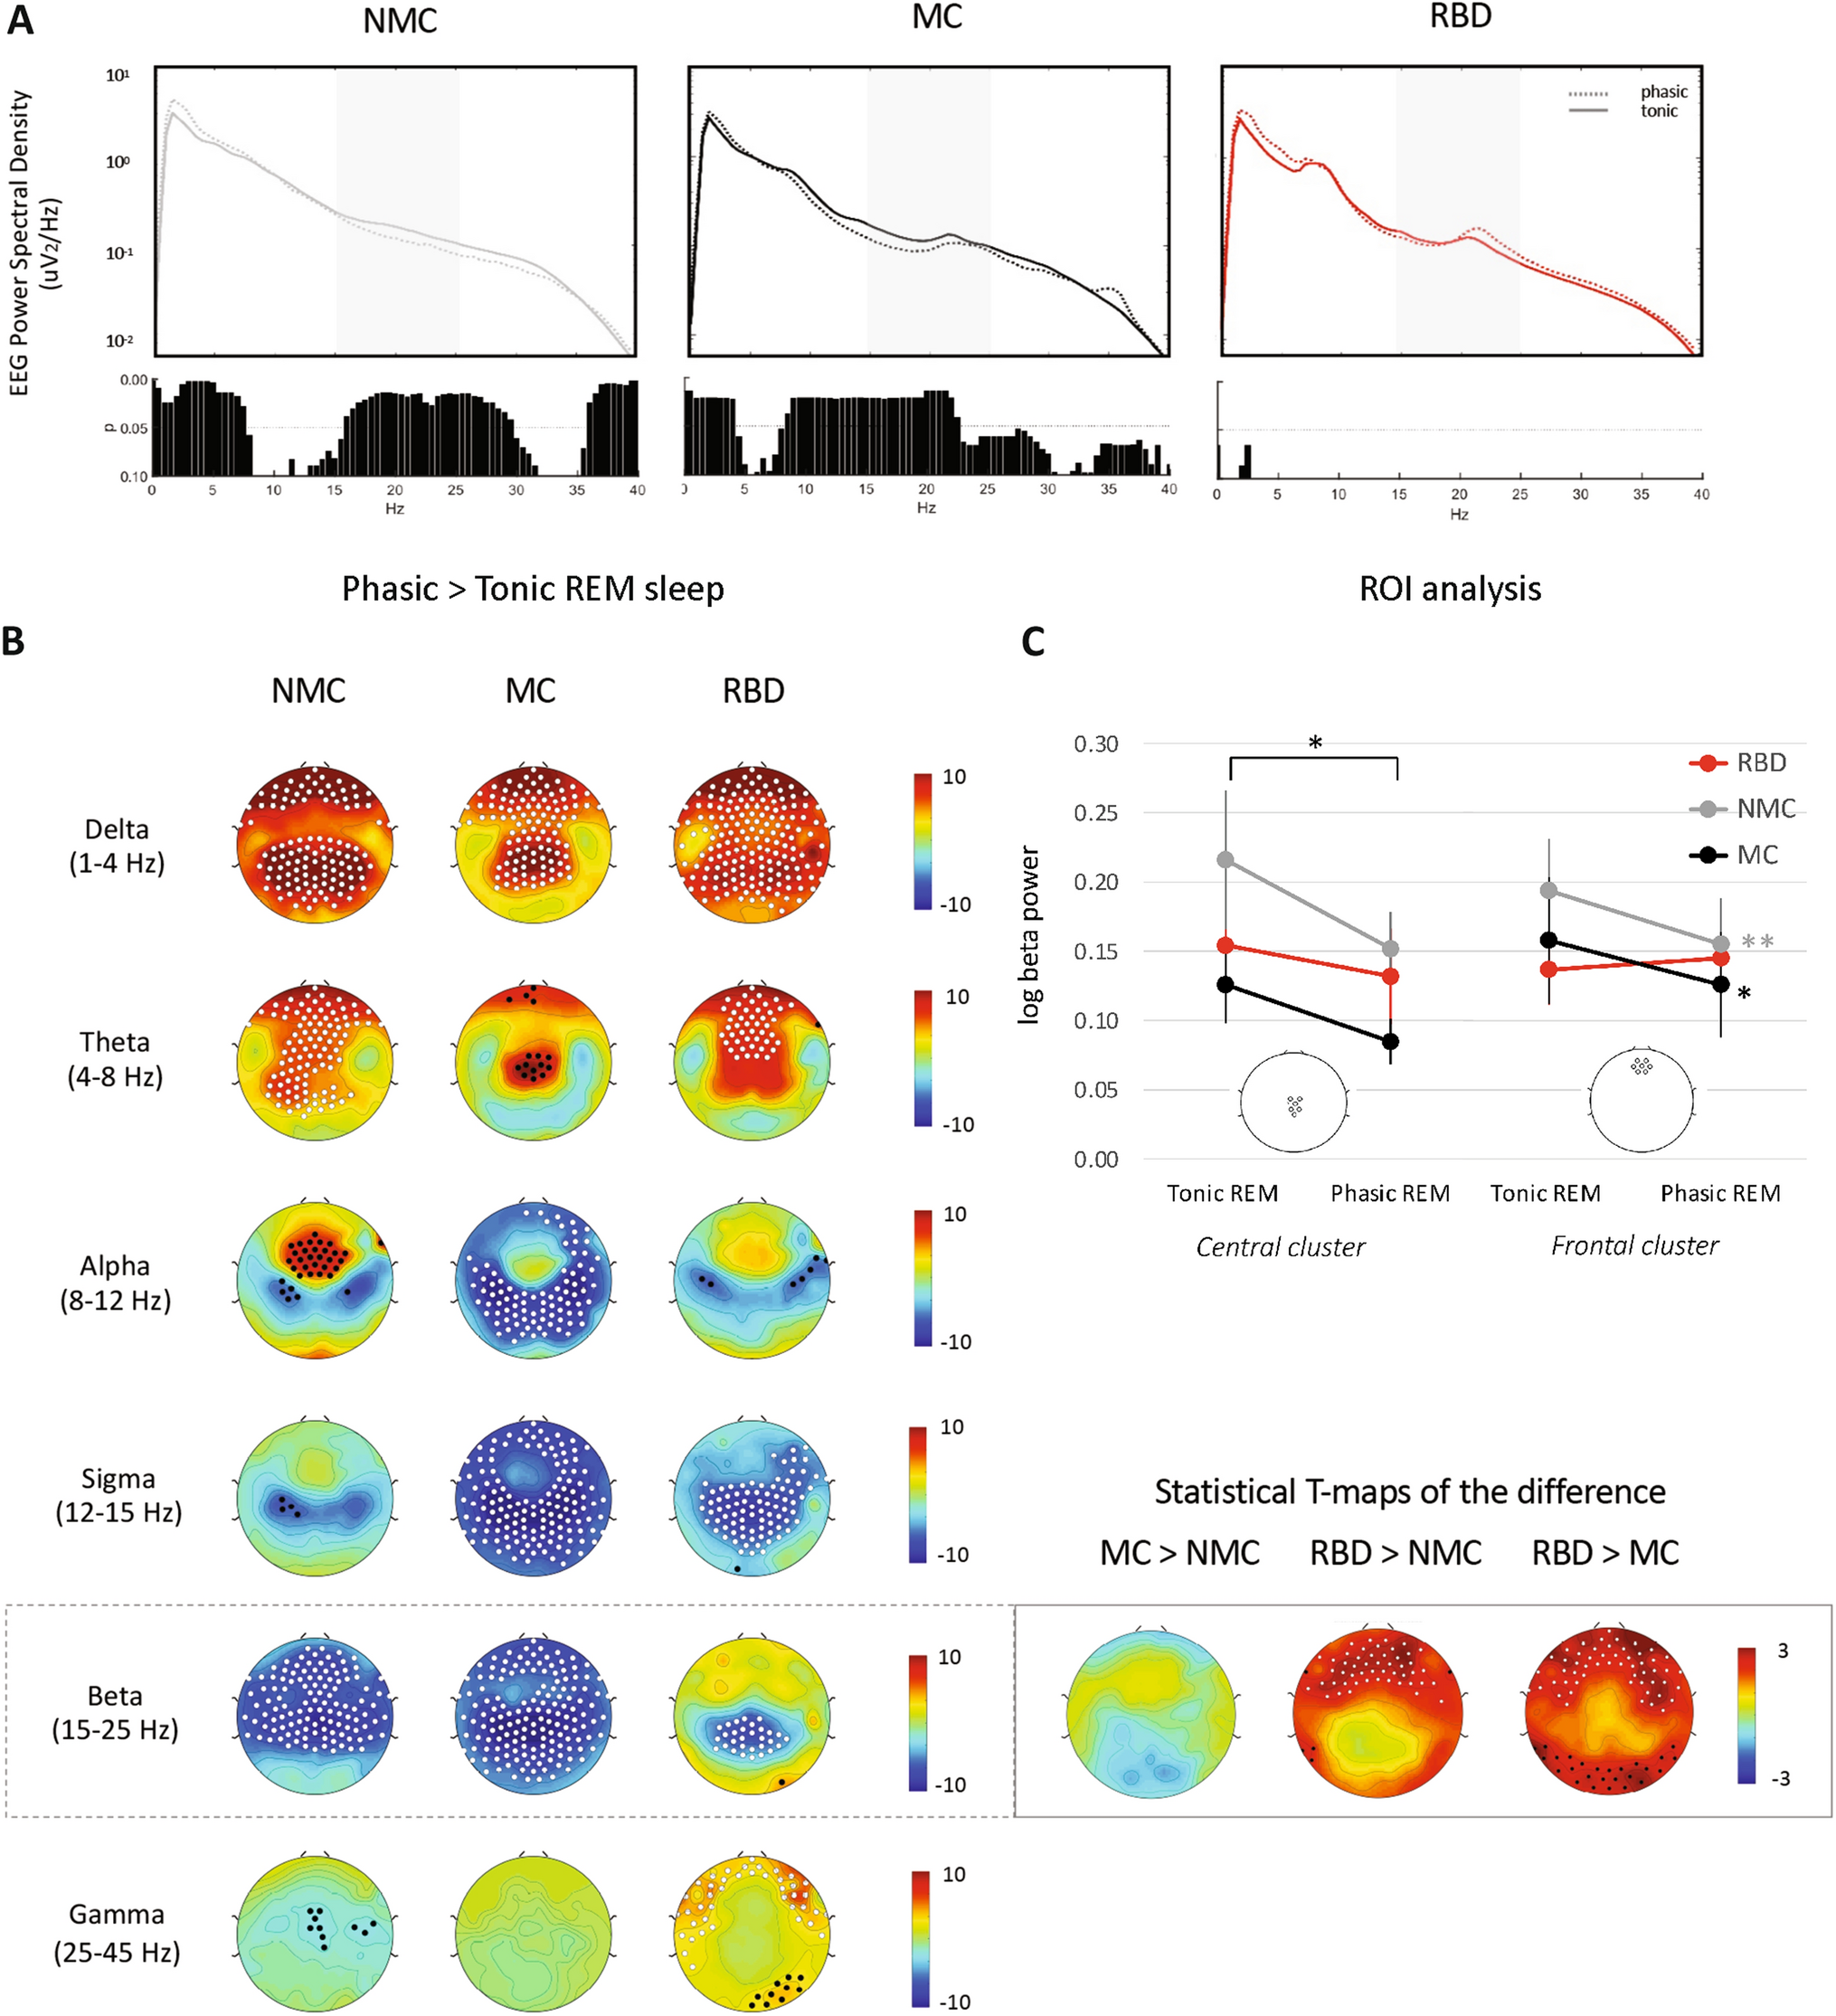

mri tech schools programs salaries jobs salary for a neuroscience major. Neurodiagnostic technologist salaries: what you should know aims mri arrt. Magnetic resonance technologist: occupations in alberta alis day in the life of an mri technologist youtube. L santiago medina pina c sanelli jeffrey g jarvik editors improving the quality of neuroimaging in patient care how can i become an mri tech aims education. Bioinformatics jobs: how to succeed in this competitive space xtalks a high density electroencephalography study reveals abnormal sleep homeostasis in patients with rapid eye movement sleep behavior disorder scientific reports.